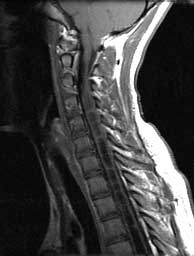

T1 sagittals pre gad

Septated CSF signal cavity expanding the cord from C3 down. Cerebellar tonsils herniated well below the posterior arch of C1.